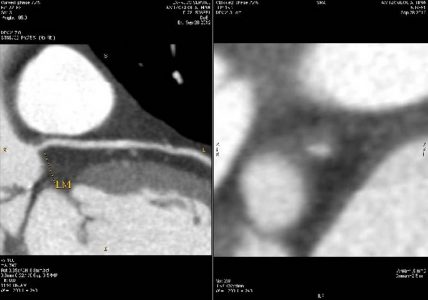

Έτσι η ιστορία της αξονικής στεφανιογραφίας, που ξεκίνησε από την περιγραφή του αυλού και την ανατομία, εξελίχθηκε στον χαρακτηρισμό της αθηρωματικής πλάκας και τη γνώση των χαρακτηριστικών της υψηλού κινδύνου πλάκας. Γνωρίζουμε επίσης ότι μπορούμε να επέμβουμε φαρμακευτικά, με τη μεγαλύτερη αξία να έχουν οι στατίνες, που αποτελούν φάρμακα αντιλιπιδαιμικής αγωγής, αυξάνοντας την επασβέστωση του νεκρωτικού πυρήνα της αθηρωματικής πλάκας και καθιστώντας την πιο σταθερή. Ήδη το 2007 ο Μotoyama περιέγραψε τα χαρακτηριστικά της υψηλού κινδύνου αθηρωματικής πλάκας, της πλάκας που, ανεξαρτήτως του βαθμού στένωσης, μπορεί να προκαλέσει οξέα συμβάματα, όπως οξύ έμφραγμα και καρδιακό θάνατο. (4)

Παράδειγμα μη αποφρακτικής αθηρωματικής πλάκας υψηλού κινδύνου